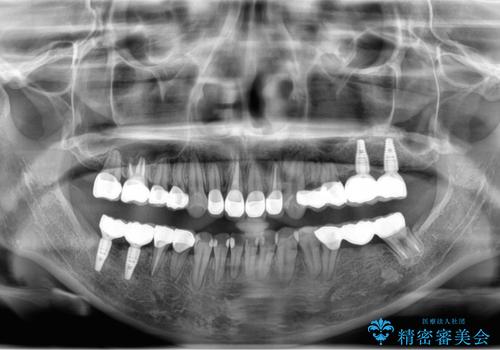

上下の歯は、上顎の歯が相対的に前に位置する咬合関係で押し出されるように前歯に角度がついている状態です。

咬合関係の改善、前歯の角度、がたつきを改善するため、マイクロインプラントを用いて上顎の奥歯を後方へ移動させていきます。

矯正治療後、前歯のがたつき、咬合関係が改善され満足いただくことができました。